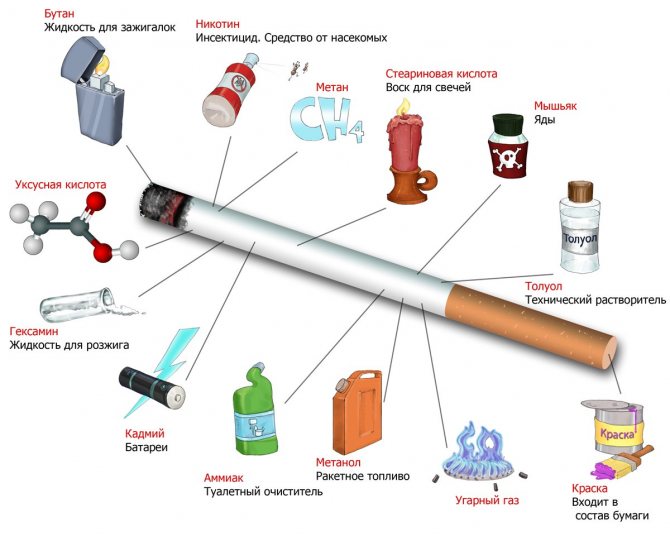

- Куріння . Напевно ви не раз бачили страшні попередження на пачках сигарет про шкоду куріння для зубів і ясен. Жахливі фотографії хворих ротів поміщені туди не випадково. Комбінація поганий догляд за зубами і хімічних сполук з тютюнового диму – пряма дорога до тяжкого запалення пародонту і втрати зубів. Зловживання сигаретами також різко знижує ефективність проведеного лікування, підтримуючи запалення і запобігаючи регенерацію тканин.

Токсичні речовини в сигареті - Неякісна і нерегулярне чищення зубів . Це основний фактор, що приводить до утворення ясенних кишень, який потрібно усунути в першу чергу.